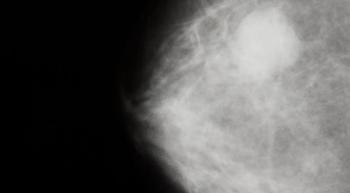

Research presented at the 2019 San Antonio Breast Cancer Symposium (SABCS) had a significant effect on the standard of care for patients with HER2-positive metastatic breast cancer, explained Erika P. Hamilton, MD.